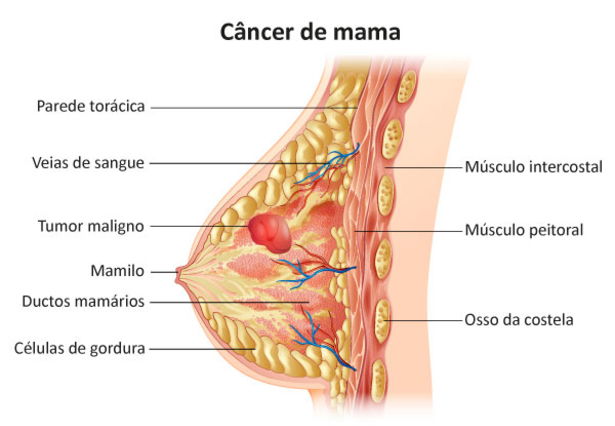

CÂNCER DE MAMA

O câncer de mama ocorre devido à proliferação desordenada de células anormais na mama, formando um tumor que pode invadir outros órgãos. É o tipo de câncer mais comum entre as mulheres no Brasil, atrás apenas do de pele não melanoma

Pontos fundamentais:

- Prevenção e Diagnóstico: A mamografia é o exame principal para detecção precoce, sendo recomendada pelo Ministério da Saúde para mulheres de 50 a 69 anos a cada dois anos.

- Sintomas: Fique atenta a nódulos (caroços) fixos e indolores, alterações na pele da mama (semelhante à casca de laranja) ou saída espontânea de líquido pelos mamilos.

- Fatores de Risco: Incluem envelhecimento, fatores genéticos, obesidade, sedentarismo e consumo de álcool.

Quando diagnosticado precocemente, as chances de cura são significativamente maiores.

Você gostaria de saber mais sobre como realizar o autoexame ou onde encontrar centros de atendimento pelo SUS?

Esse texto é apenas para fins informativos. Para orientação ou diagnóstico médico, consulte um profissional. As respostas da IA podem conter erros